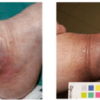

Ulkus pada kaki biasanya dihubungkan gangguan sirkulasi pembuluh darah arteri atau vena yang menyebabkan jaringan kekurangan suplai oksigen, seperti pada penderita diabetes mellitus, penyakit buerger, atau klaudikasio intermiten. Kerusakan sistem saraf otonom menyebabkan sensasi rasa menghilang, disertai kulit mengering dan menebal sehingga pecah-pecah dan terjadi ulkus.[1-3]

Kondisi ini sering ditemukan pada kaki, yaitu area yang memiliki aliran pembuluh darah paling jauh dari jantung, dan yang paling sering mendapatkan tekanan atau gesekan dari luar. Apabila tidak diterapi dengan baik, maka dampak yang disebabkan oleh ulkus akan semakin berat seperti gangren, osteomyelitis, sepsis, hingga amputasi.[1-3]